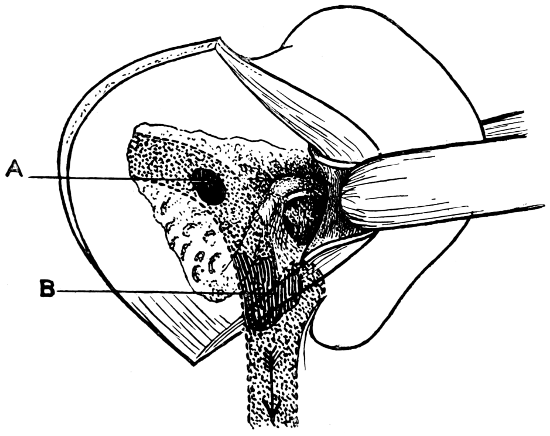

| 74 A and B. To illustrate the extension of disease from the tympanic cavity and the surgical anatomy of that region (after Hunter Tod) | 251 |

| 90. To illustrate the operations on the Gasserian ganglion | 317 |

| 91. To illustrate the operations for exposure of the Gasserian ganglion | 321 |